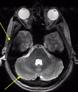

Recently FDA-approved 7 Tesla (T) MRI can provide improved signal-to-noise ratio, resolution, and image contrast when compared with standard clinical MRI scanners (usually 1.5T or 3T). However, proton imaging at higher frequencies (~300MHz) and shorter wavelength (~13cm in brain tissues) can lead to inhomogeneities in the images and potentially cause high localized radiofrequency (RF) power deposition in the tissue. The Tic-Tac-Toe (TTT) RF coil system provides improved homogeneity and reduced power deposition. It is achieved thanks to an innovative coil design and a methodology of operation. Several clinical MRI sequences have been performed and compared with commercial RF coils, demonstrating the superior performance of the Tic-Tac-Toe RF coil system. Numerous clinical studies including NIH funded studies (~2,000 subjects) are currently being conducted using this coil at the University of Pittsburgh.

b) a) c) The Tic-Tac-Toe (TTT) radiofrequency head coil for 7T MRI Fig 1: in a), the implemented 16-channel TTT transmit RF coil; in b), the computational RF coil in c), the implemented RF coil with an 32-channel receive insert Fig. 2: The B1+ (magnetic field responsible for spin excitation) field homogeneity is highly degraded at 7T MRI due to a higher operational frequency (~297MHz). The TTT presents a more homogeneous field distribution when compared with the NOVA coil (a commercial coil) [1]. Measured Tic-Tac-Toe Measured Nova coil Regions with low B Simulated Tic-Tac-Toe B + maps in the brain: TTT vs NOVA RF coils TTT coil NOVA coil TTT coil NOVA coil Image comparison with the 32-channel NOVA commercial RF coil a) b) Fig. 3: In a), Turbo spin echo (TSE) sequence using the TTT coil with resolution of 0.4x0.4x2mm. In b), the same TSE sequence acquired with the commercial NOVA coil. In c), FLAIR sequence acquired with TTT coil with resolution of 0.7x0.7x2mm. In d), the same FLAIR sequence acquired with NOVA coil. The arrows point to regions of dark spots in the NOVA coil images and compare with similar regions on the TTT coil images [1]. c) d) High-resolution susceptibility weighted images showing cortical microvessels Fig 4 SWI images acquired at 0 2x0 2x1 5mm resolution In a) an axial slice of the whole brain image acquisition In b) and c), zoomed versions of a), detailing the micro-structures a) b) c) High resolution angiography without contrast agents 380μm a) b) Fig 5: Maximum intensity projection orientation and small vessels detectability isotropic image showing whole brain isotropic acquisition In d), 0 20mm are only detectable at higher resolution

Finger tapping task: activation of Functional MRI a) Diffusion MRI and fiber tracking Post-mortem a) a) b) Fig 7 In a), an structural MPRAGE image acquired at 0 75mm isotropic (skull removed using FSL package) In b), fiber tracking based on DTI acquisition, 64 directions, 1 5mm isotropic resolution The colors are defined for different orientations of the fibers Fig 8: In a), susceptibility weighted images acquired at 0 35mm isotropic, 32 min acquisition time, in a post-mortem brain fixated with formalin In b), a photograph of similar slice in the same brain Table 1: 7T MRI studies conducted at the RF Research Facility at University of Pittsburgh White matter legions (circle): Multiple Sclerosis study Stroke (circle): sickle cell disease study Automatic hippocampus segmentation: Midlife Neurocognitive Lacunar infarct (arrow): depression study White matter hyperintensities (arrows): Healthy Brain aging study (left) and Small Vessels disease in preclinical Alzheimer’s disease study (right) Fig 9: Sample of some studies listed in Table 1 using the developed 16 array (Fig a) There are 4 completed studies and 13 ongoing patient studies with approximated 2 000 patients scheduled FUTURE DIRECTIONS 64-channel Tic-Tac-Toe RF transmit coil for 7T MRI 0 Fig 10: In a), the 64-channel transmit coil computational modeling [2] To improve the field of view of the projector/monitor in fMRI studies, the frontal panels can be removed, resulting in a 56-channel coil In b), one assembled side of the coil In c), simulated B1+ field distribution: for an 8kW power amplifier capabilities (default in older 7T MRI scanners) a homogeneity (measured by the coefficient of variationCV) of 15 2% is achieved in the brain For an 16 kW power amplifier (available for the recently FDA approved Siemens 7T MAGNETOM Terra), an CV of 10 6% can be achieved in the brain 16 kW power amplifier: 8 kW power amplifier: a) b) c) max